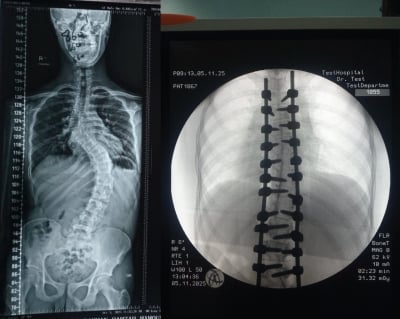

• إنجاز طبي في مستشفى الأمير حمزة: تصحيح جنف حاد بالعمود الفقري